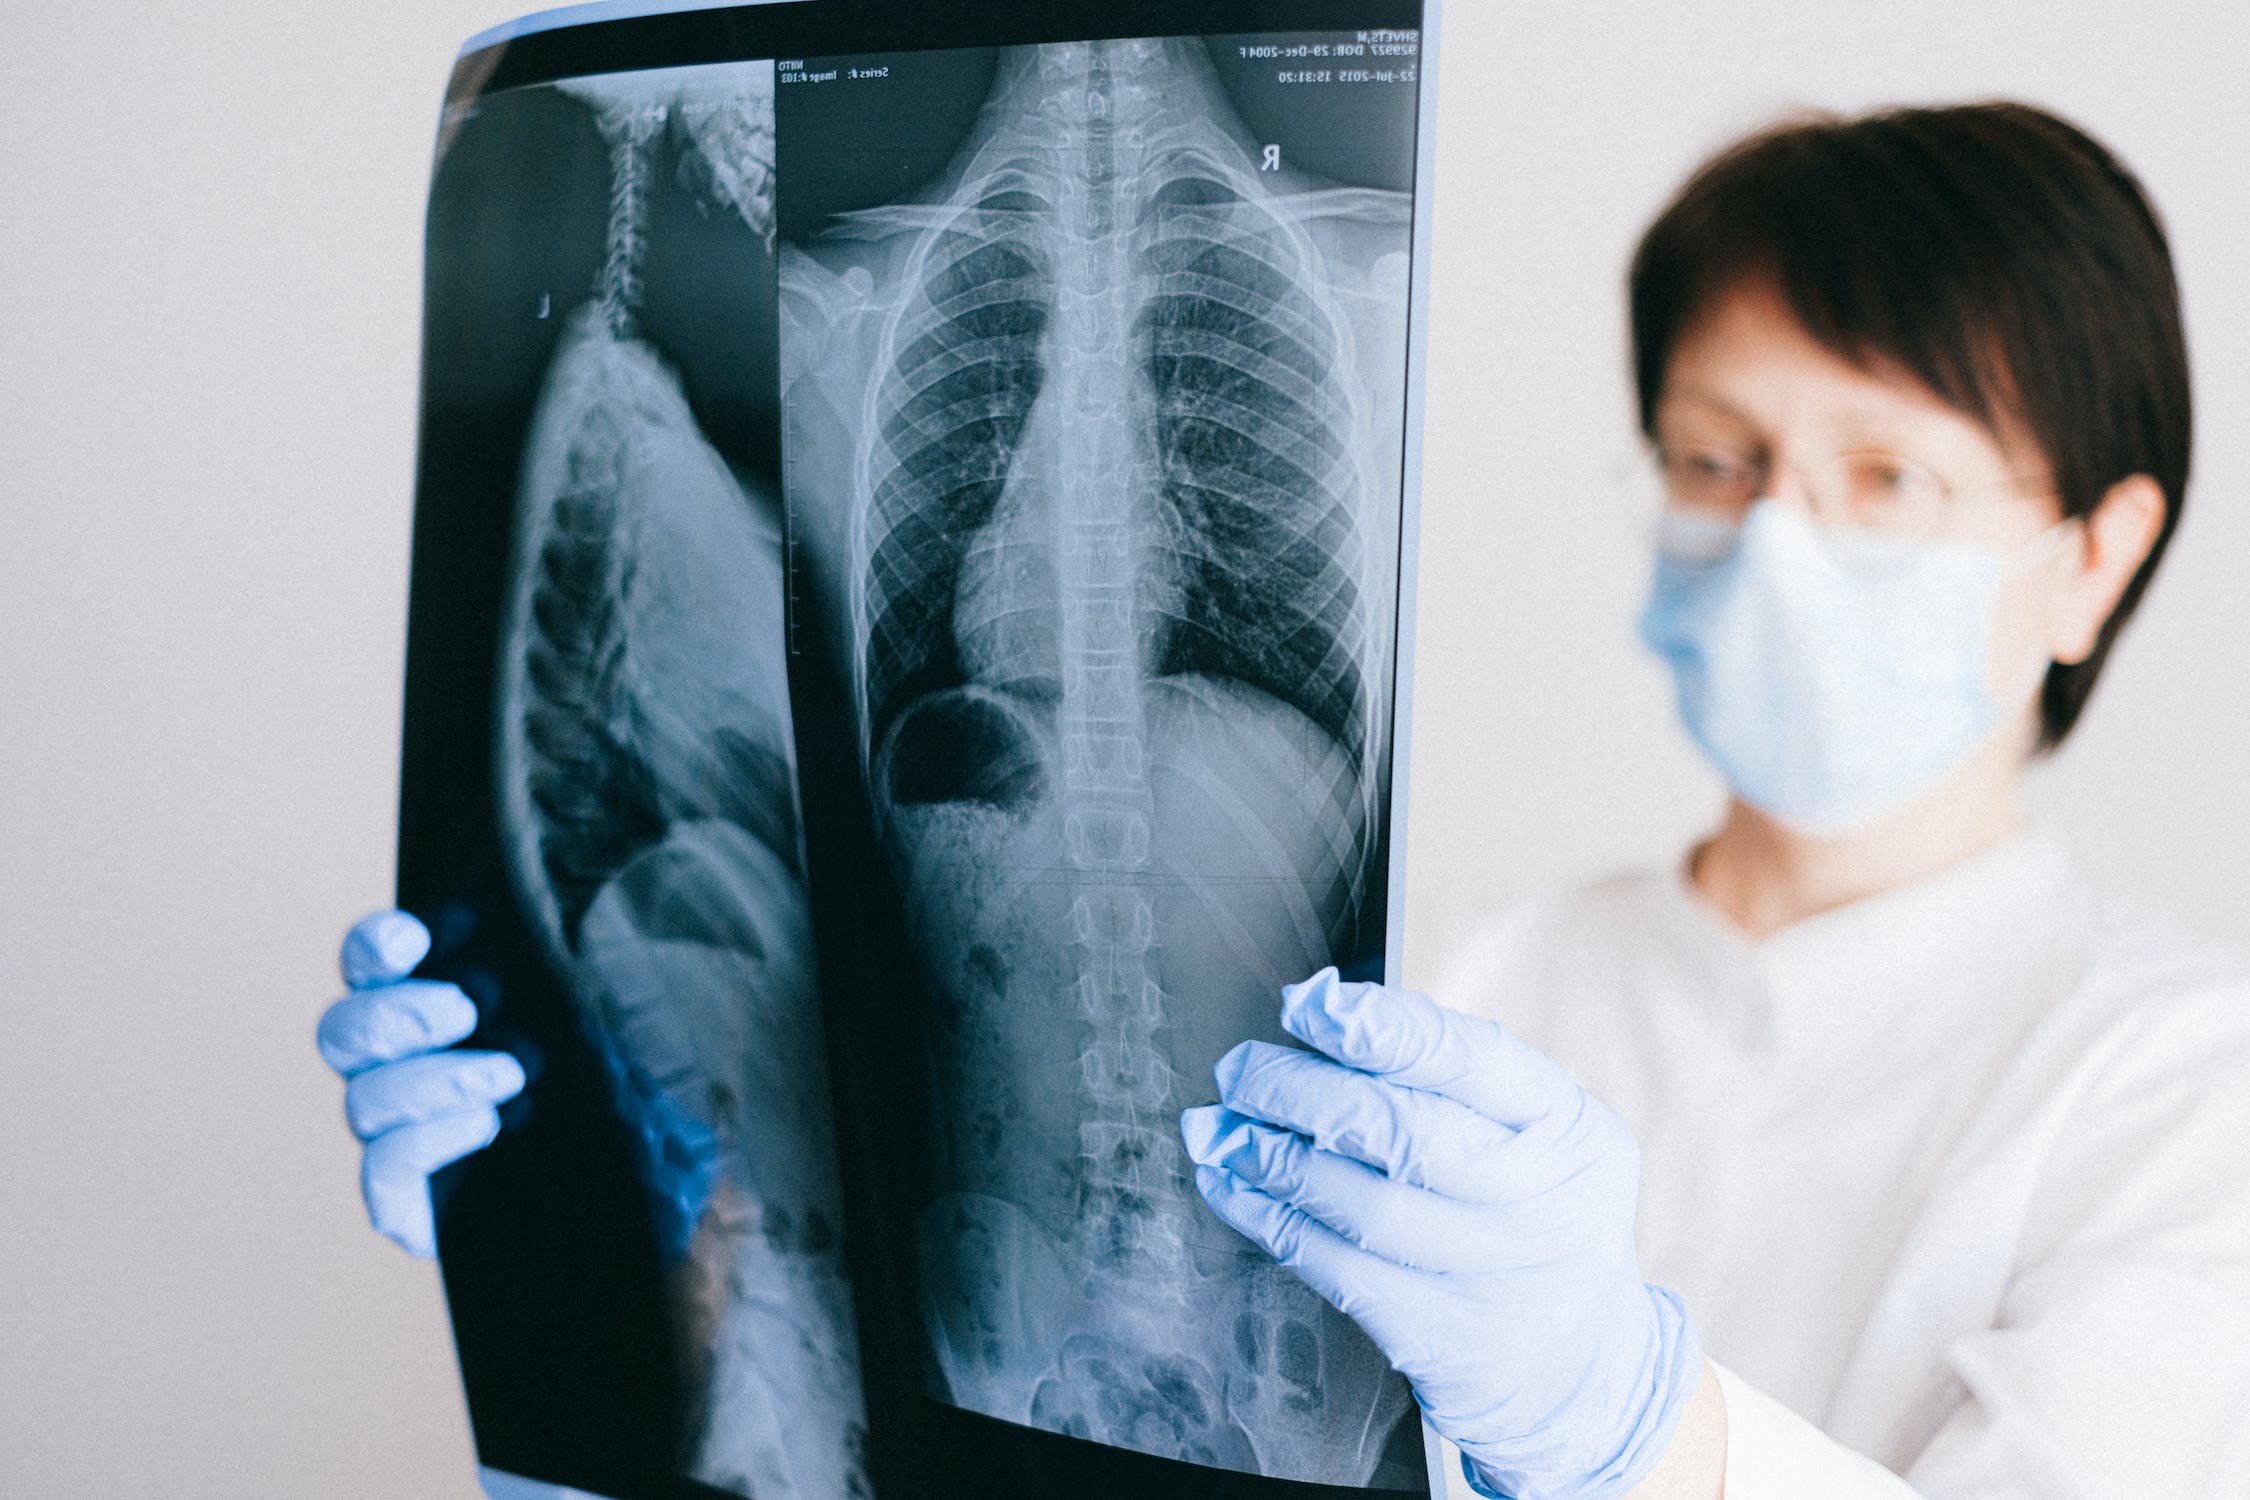

① 흉부 X선 촬영

X선 검사방법으로는 실제 크기로 촬영하는 흉부 직접촬영과 70㎜, 100㎜ 크기의 축소된 사진으로 찍는 간접촬영이 있는데, 여러 사람을 집단으로 검사할 경우에는 간접촬영을 많이 이용합니다.

소견에 따라 초감염 결핵과 재활성화 결핵으로 나뉘며 흔히 전자는 소아 결핵, 후자는 성인 결핵으로 분류하기도 하며 인체면역결핍 바이러스(HIV) 감염자는 초감염 결핵 소견이 주로 나타나는 것으로 알려져 있습니다.